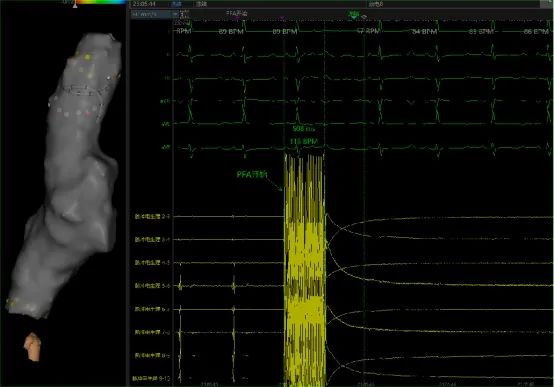

心脏脉冲电场消融术试验中上腔静脉隔离前后的电位比较(受访对象供图)

作为一项具有组织选择性的非产热技术,这种新型的脉冲电场消融技术,可在消融过程中产生微秒级脉冲电场,并在细胞膜上产生纳秒级微孔,实现“电穿孔”。“相较于平滑肌和神经细胞,心肌细胞对脉冲电场的阈值最低,从而使得在脉冲电场消融过程中心肌细胞最先坏死。因此,使用此次研发成功的心脏脉冲电场消融系统,在房颤手术过程中,就可避免目前主流的消融技术可能产生的肺静脉狭窄,食道损伤及膈神经损伤等并发症。”高进年说。